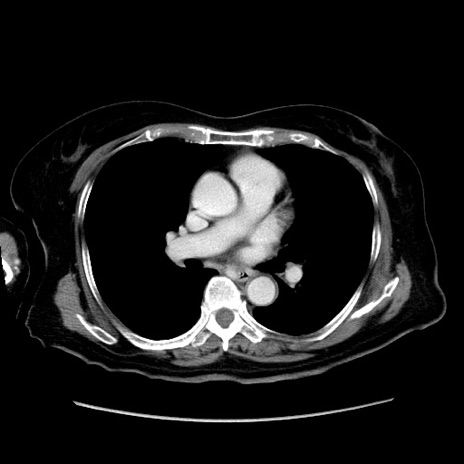

冠状断像

症例19(横断像)

【症例】80歳代女性

【主訴】下腹部痛

【現病歴】約8時間前より下腹部痛の出現あり、救急外来受診。

【既往歴】両側付属器切除

【身体所見】意識清明、下腹部正中に手術痕あり、その部位に一致して圧痛と反跳痛あり。腸蠕動音は亢進。

【データ】WBC 9300、CRP 0.15